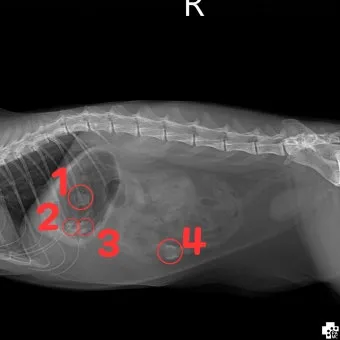

고양이가 이물질을 삼켰을 때는 2-3시간 내 골든타임을 활용한 신속한 응급처치가 생명을 좌우합니다. 평소 구토를 하지 않던 젊은 고양이가 3회 이상 구토한다면 이물질 섭취 가능성이 97%에 달한다는 수의학 통계가 있어요.

식욕부진, 기력 저하, 그리고 구토는 이물질을 삼켰을 때의 주된 증상이다. 특히 장이 막히면 하루 10번 이상 구토를 하기도 한다. 이런 증상들은 시간이 지날수록 생명을 위협할 수 있어요.

• 3회 이상 연속 구토 (특히 평소 구토 안 하던 고양이)

• 하루 10회 이상 구토 (장폐색 가능성)

• 복부 팽창과 만졌을 때 단단함